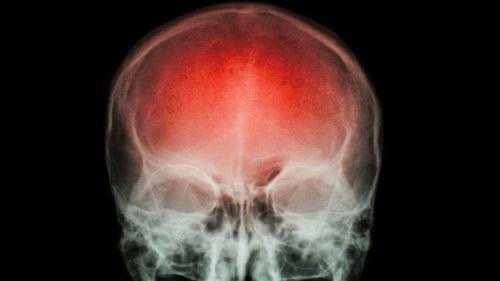

O acidente vascular cerebral (AVC) é uma emergência médica que pode mudar a vida de uma pessoa em questão de minutos. Ele ocorre quando o fluxo sanguíneo para uma parte do cérebro é interrompido ou reduzido, causando a morte de milhões de neurônios por falta de oxigênio e nutrientes. Em um AVC, cada minuto conta: podem morrer até 1,9 milhão de células cerebrais por minuto. Por isso, a detecção precoce e o atendimento médico imediato são determinantes para evitar sequelas graves ou até mesmo a morte.

Os avanços tecnológicos em imagens diagnósticas, como tomografia computadorizada, ressonância magnética e angiografia, permitem que os profissionais de saúde visualizem com precisão as áreas afetadas do cérebro, identifiquem o tipo de AVC e tomem decisões clínicas em poucos minutos. Com essas inovações, os tratamentos podem ser iniciados de forma mais rápida e eficaz, aumentando significativamente as chances de recuperação dos pacientes.